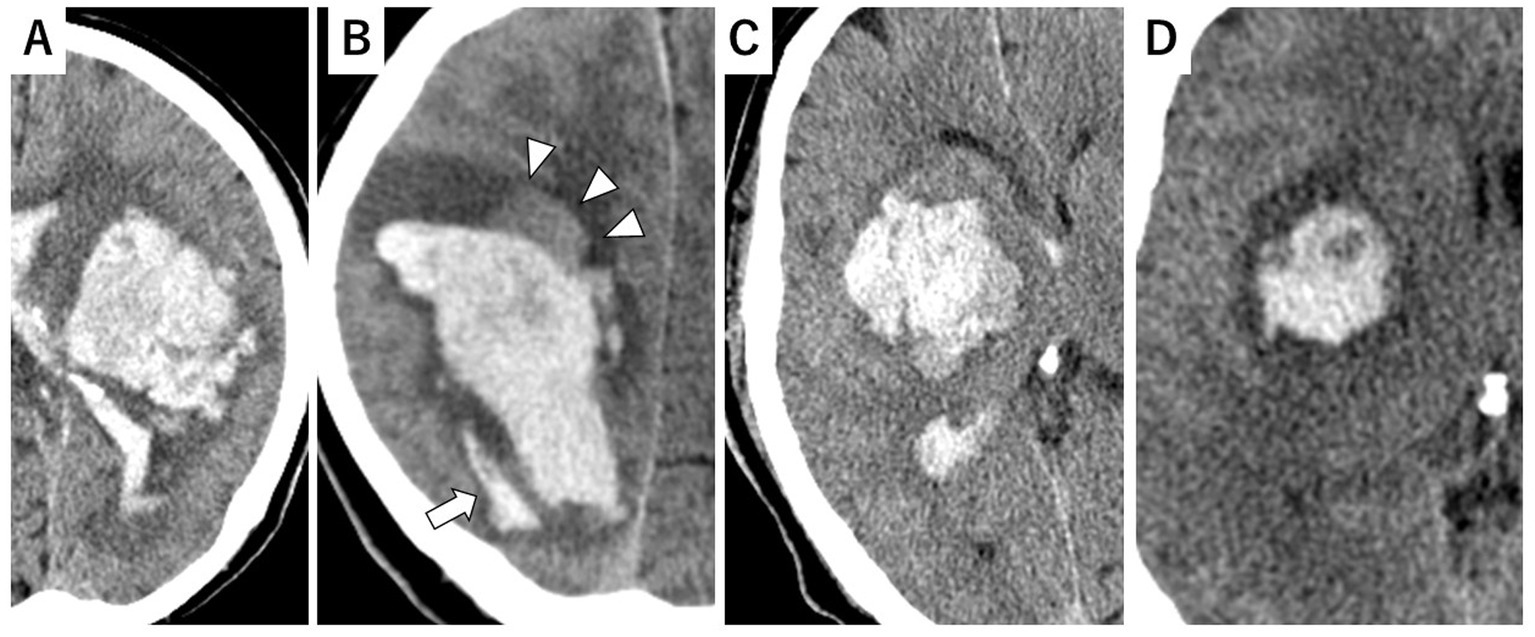

The CT morphology of the hematoma was assessed based on its margin configuration and Hounsfield unit (HU) characteristics. An irregular hematoma margin was defined as meeting at least one of the criteria for the island sign or the satellite sign. Heterogeneous hematoma density was defined as meeting at least one of the criteria for the blend sign or the black hole sign. The following imaging signs were defined as follows (7, 9–11):

Island sign: Defined as three or more small hematomas scattered apart from the main hematoma, or more than four small hematomas partially or completely connected to the main hematoma (Figure 1A).

Satellite sign: Defined as high-density lesions observed around the hematoma (Figure 1B).

Blend sign: Defined as a hyperattenuating area blends with an adjacent relatively hypoattenuating region, with a well-defined margin (Figure 1C).

Black hole sign: Defined as a relatively hypoattenuated round, oval, or rod-shaped area within a hyperattenuated hematoma (Figure 1D).

Figure 1

Representative examples of CT markers. (A) Island sign. (B) Satellite sign (allow) with blend sign (allow heads). (C) Blend sign. (D) Black hole sign.